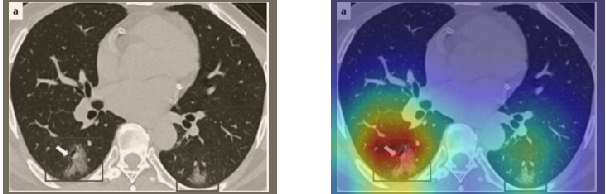

Figure 16 shows various CT scans where only one lung is visible. The CT scans are also extracted from the paper [58] and show different CT manifestations of COVID-19 pneumonia marked by red squares. The InceptionV3 model is capable to classify them correctly as COVID-19, although it is trained on CT scans where the entire lung is visible. Intriguingly, when applying Grad-CAM we can see that all regions of abnormalities are accurately localized. This also proves the potential of our model to detect COVID-19 abnormalities in CT images outside the dataset used for training.